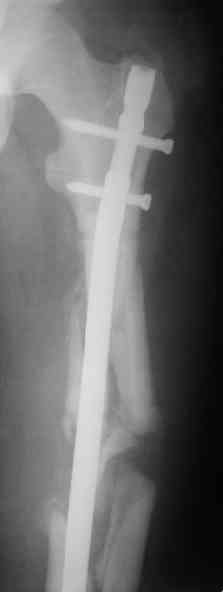

Судя по уровню перелома, винты в шейку избыточны, подойдет и диафизарный гвоздь. Все, что нужно, это тиски и труба. Загнуть сразу ниже отверстий градусов на 8-10, и вся недолга. Последние годы у нас это рутинная практика. Предызогнутые еще с завода гвозди неудобны тем, что они уже правый-левый.

Согласен, что закрытый реостеосинтез с рассверливанием и коррекцией оси - это то, что надо. Мы бы ввели в центральный отломок статических 2-3 винта, и один динамический винт в дистальном отломке.

Вот несколько. С тисками и трубой на днях сделаем.

Саша, последний штифт, пожалуй, перегнули?

Там заход сделан как для прямого штифта, не через вертел.